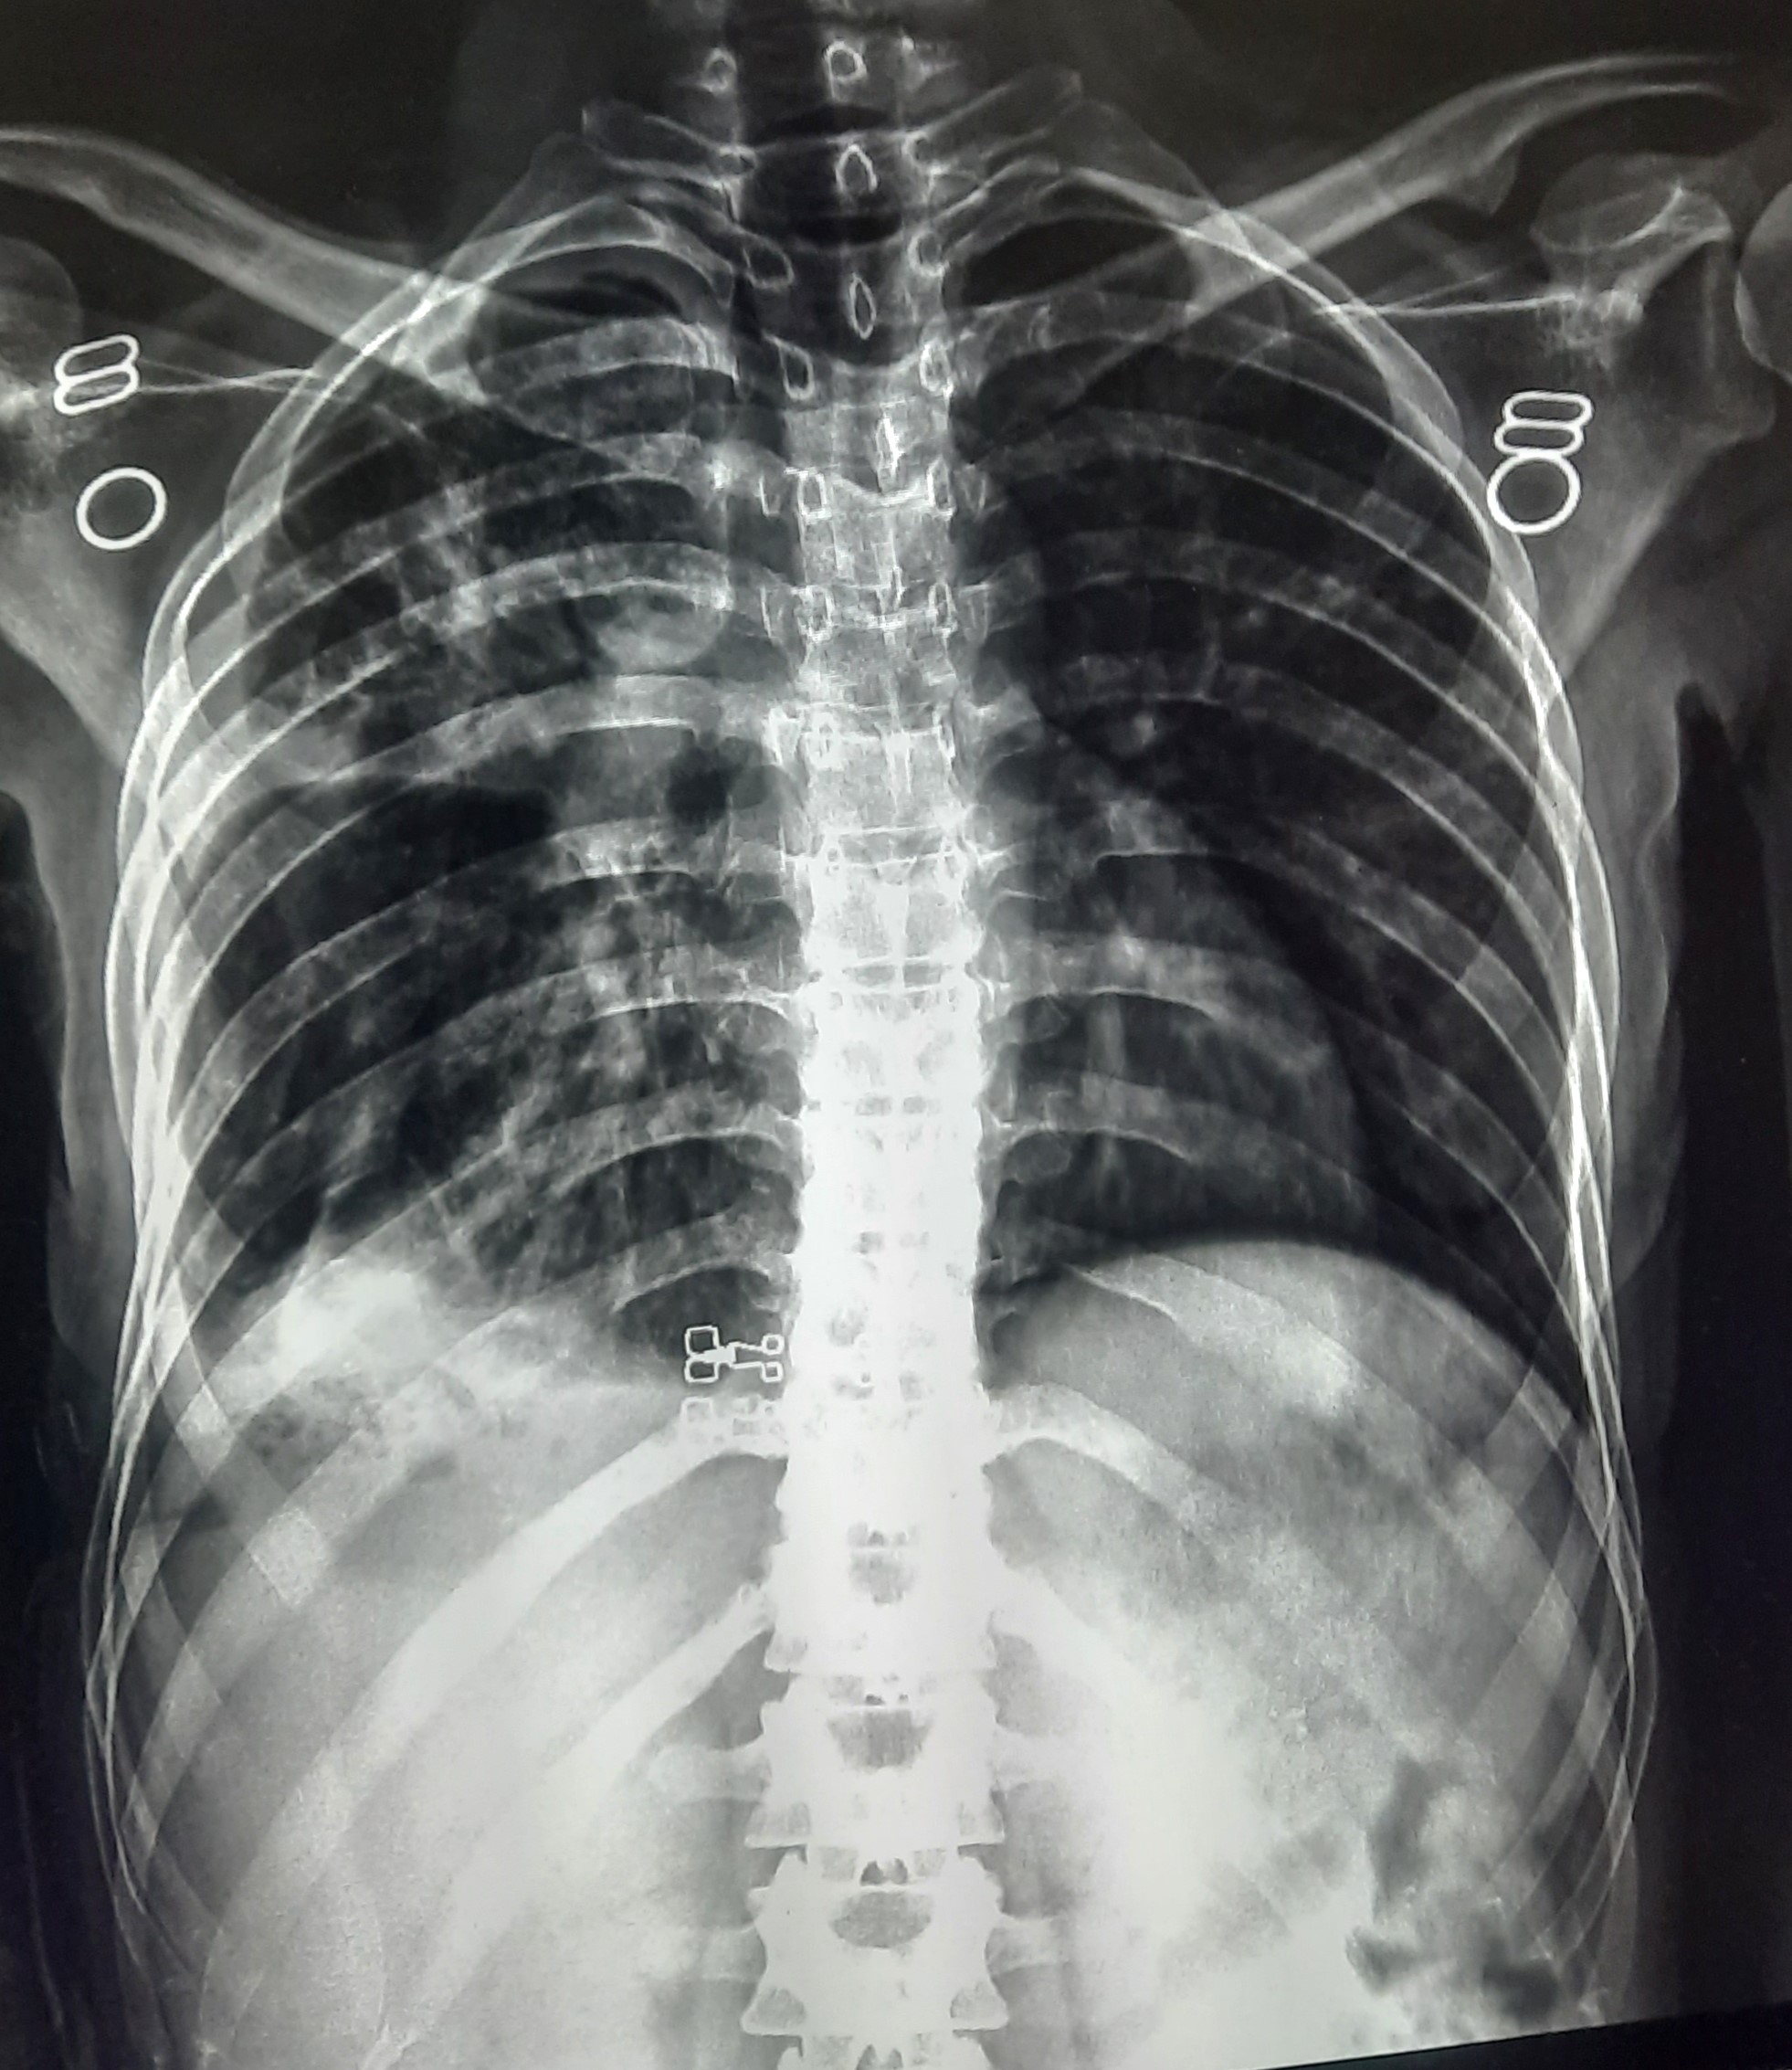

| 52 | IGGMC, Nagpur, Nagpur | P2 | 29-4420 | Hamida Bano | Consent taken on Paper | 56 Yrs. |

Provisional Diag : Post TB Sequelae With Reactivation?

Final Diag : Post TB Sequelae |

Post TB Sequelae | Tracheal Pull Left Side, Left Mid Zone & Upper Zone Fibro cavitary Lesion Present, Compensatory Right lung Hyper Infiltration Present, Few ill-defined Bilateral Lung Opacity Presnt | Abnormality visible on x-ray |